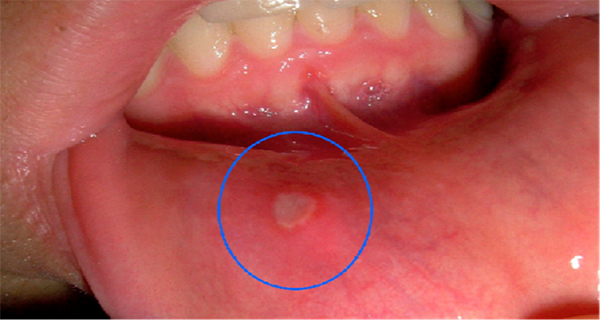

Old  Default Chữa NHIỆT MIỆNG nhanh và hiệu quả

Những vết loét nhỏ gây đau đớn khủng khiếp, và đôi khi thậm chí cản trở việc ăn thực phẩm. Loét miệng là do nhiễm virus vô hại, chỉ kéo dài vài ngày đến một tuần, nhưng đôi khi lâu hơn nếu không được điều trị.